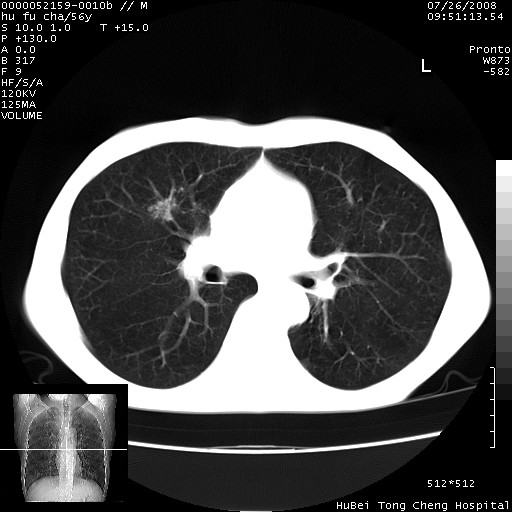

以下是引用zsl6918在2008-8-25 22:47:00的发言:[br]胸骨,胸椎及肋骨均可见多发转移表现,肝内低密度结节不除外转移。原发灶可能在右肺。双侧可见支扩表现。